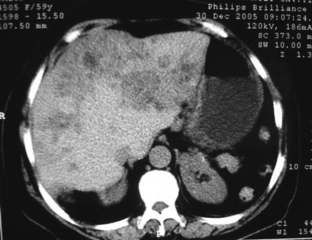

Böbrekte kistik lezyon, genellikle böbrek dokusunda sıvı dolu kesecikler (kistler) oluşturan, benign (iyi huylu) ya da malign (kötü huylu) olabilen yapılar olarak tanımlanabilir. Bu lezyonlar, böbreklerin normal işlevlerini etkileyebilir ve bazı durumlarda belirti vermeden uzun süre varlık gösterebilirler. Kistik lezyonlar, genellikle görüntüleme yöntemleriyle (ultrason, bilgisayarlı tomografi, manyetik rezonans görüntüleme) tespit edilir. Kistik Lezyonların TürleriBöbreklerdeki kistik lezyonlar, birkaç farklı türde sınıflandırılabilir:

Tanı ve Teşhis YöntemleriKistik lezyonların tanısı, çeşitli görüntüleme yöntemleri ile konulmaktadır:

Rapor, sağ böbrek üst pole yerleşmiş bir lezyonu tanımlamaktadır. Bu lezyonun boyutları 35x30 mm olarak belirtilmiş ve düzgün konturlu olduğu ifade edilmiştir. Düzgün konturlu lezyonlar genellikle iyi huylu yapılarla ilişkilendirilir, ancak kesin bir değerlendirme için ek tetkiklere ihtiyaç vardır.

Egzofitk yerleşim, lezyonun böbreğin dışına doğru büyüdüğünü göstermektedir. Bu durum, lezyonun doğasına dair ipuçları verebilir. Solit lezyonlar, genellikle tek başına bulunan ve çevresinde yayılım göstermeyen oluşumlardır. Ancak, bu tür lezyonların değerlendirilmesinde görüntüleme yöntemlerinin önemi büyüktür.

Rapor, kontrastlı tüm batın BT (Bilgisayarlı Tomografi) önerilmektedir. Bu tetkik, lezyonun özelliklerini daha ayrıntılı incelemek, çevresindeki dokularla olan ilişkisini değerlendirmek ve olası metastaz veya yayılım durumunu gözlemlemek açısından büyük önem taşımaktadır.

Sonuç olarak, bu lezyonun iyi huylu mu yoksa kötü huylu mu olduğunu kesin olarak belirlemek için ek görüntüleme ve muayeneler gerekmektedir. Bu süreçte bir uzmana danışmanız faydalı olacaktır.